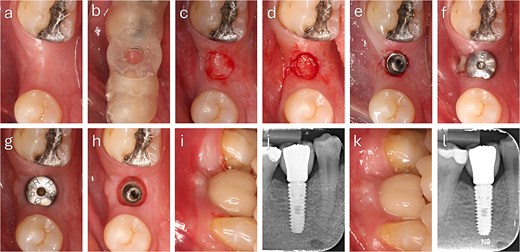

Clinical and radiographic assessments included intraoral scanning and CBCT. Guided surgeries were digitally planned using Exoplan 3.1 (exocad, Germany), and the surgical guides were printed [8]. In the first and second cases, the total buccal tissue complex (bone + mucosa) measured ~2.20 and 1.83 mm, respectively, when assessed from the most buccal implant crest to the external mucosal surface (Fig. 1).

Preoperative digital assessment of buccal soft and hard tissue thickness using cross-sectional CBCT planning views. The measured distances represent the combined buccal bone and mucosal thickness from the buccal crest of the planned implant to the external surface of the mucosa. (a) Case 1: Total mid-buccal tissue thickness ≈ 2.20 mm; vertical thickness ≈ 2.50 mm. (b) Case 2: Total mid-buccal tissue thickness ≈ 1.83 mm; vertical thickness ≈ 3.11 mm.